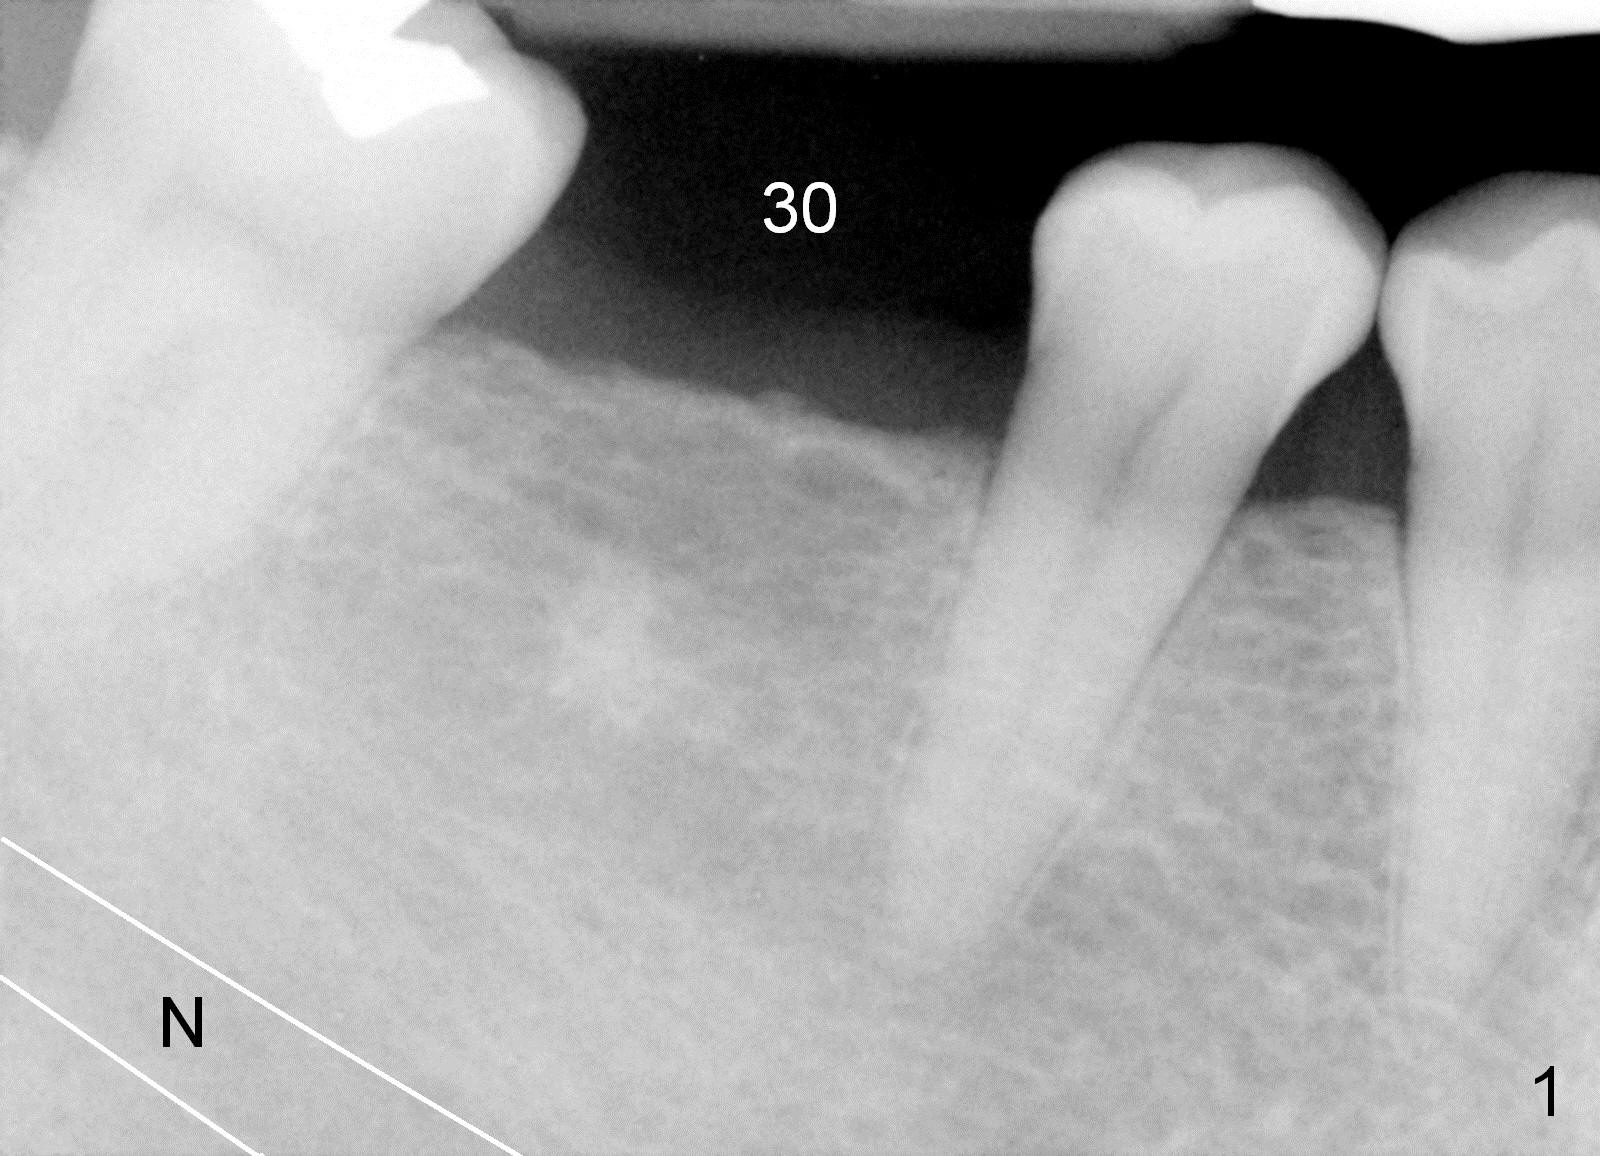

Six years ago, a 38-year-old patient presented to our office for new patient exam. She was scared of dentistry, but 3 of the third molars needed extraction. When the surgery was done painlessly, it was not too hard to persuade the patient to accept implant placement at the site of #30 (Fig.1; N: Inferior Alveolar Nerve). It was the 1st case when a 2nd implant system was adopted in the office. The implant is 3 mm shorter than the design (Fig.2). An incision was made for visibility (Fig.3). There is no bone loss 3.5 months postop (Fig.4). The crown is cemented 5 months postop (Fig.5); there is attached gingiva buccal to the implant. What surprised us the most is that she turns out to be one of the most faithful patients in our office. She never misses 6-month recall.